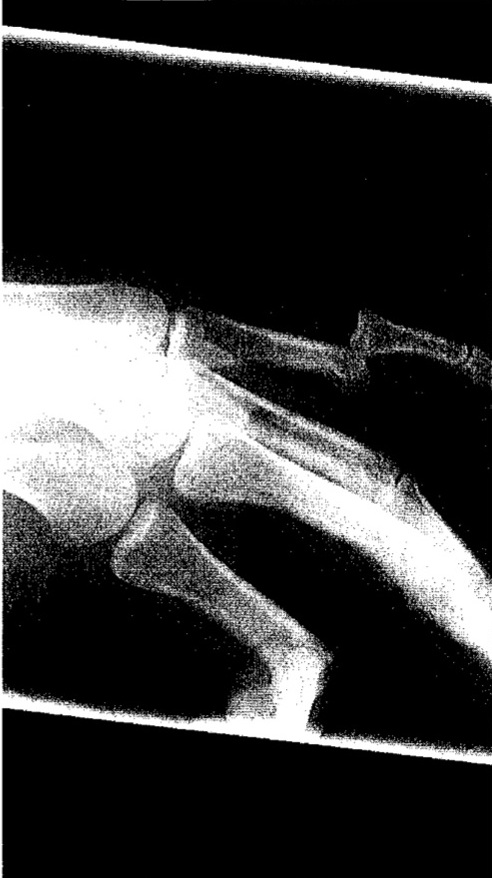

Yep. Dislocated my “pinkie” (why is it called that?) finger, TWICE, last night in a basketball game. Short version – fell, dislocated finger, looked awful, popped it back in place, felt better, moved freely, went back into the game, ball hit hand, finger dislocates again, VERY painful, afraid to pull it back in place, too light headed to drive, Courtney takes me to ER, they x-ray, numb my finger and pull it back in place.

Anyway…typing now is painful. Enough said. X- Ray picture below. If you’re really squeamish, you might not want to scroll down.

Yeah, that’s gross.